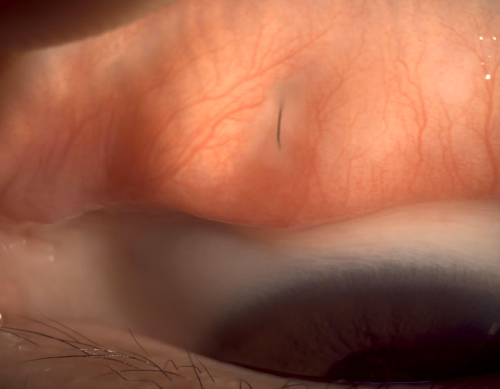

바로 전안부 사진 보시겠습니다.

마지막으로 노출된 실밥이 중간에 끊어지지 않고 매듭을 유지하고 연결되어 있는 상태로 표면이 매끄러워 보였습니다.

(마치 과거 백내장 수술 후에 한 바늘 꿰매고 나서 실밥이 있는 분들처럼, 이런 경우 실밥 제거없이 놔두는 경우도 많습니다.)